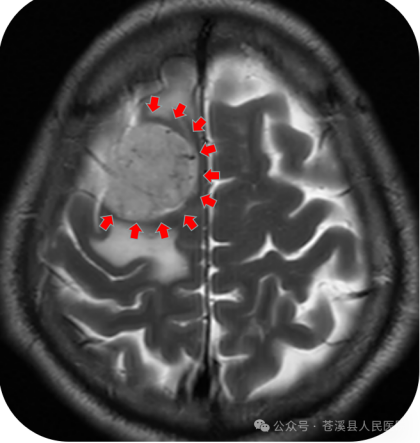

▲术前检查MRI肿瘤在大脑矢状窦旁,中央前回受压,脑水肿明显。